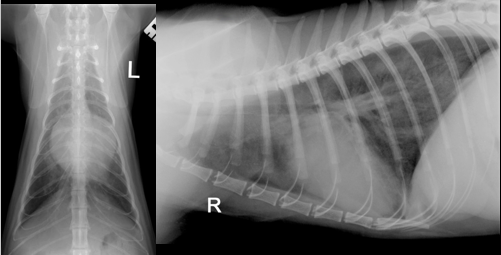

• DV and R lateral of thorax

• Both straight and minimal axial rotation. Both inspiratory and labelled. No artefacts.

• More sternal contact of the heart

• Lung pattern: Interstitial

• Vertebral heart score (4+6) = 10

• Width of heart – 2 IC (normal)

• DV – valentine shaped heart. Wide cranially = big atria. In cats its harder to guess chamber enlagement (e.g. could just be just LA and pushing to R)

• Lateral – Border obliteration (cranially). Measrure perpendicular width is bigger between 5th and 7th rib (wide and tall)

• Lungs: Increased opacity. Less opaque areas – interstitial. Alveolar pattern too

• Ventral on the lateral – increase opacity = could be fat but small amount of pleural effusion – look dorsally the lung lobes the one meet at T10 and normally in cats wont come away until T11-13.